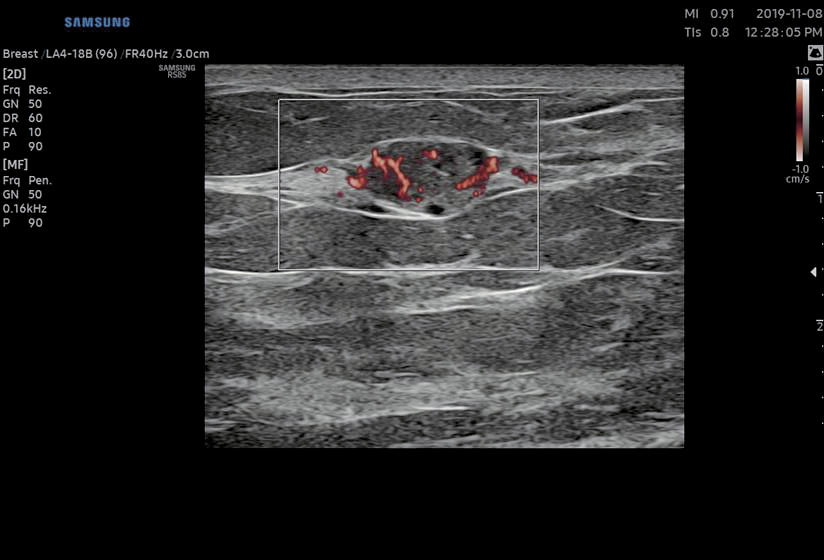

MV-Flow™ offre une alternative au Doppler conventionnel pour visualiser la microvascularisation. Des cadences images élevées et un système avancé de filtres permettent au MV-Flow™ de proposer une vue détaillée de la vascularisation par rapport aux tissus environnants avec une meilleure résolution spatiotemporelle.